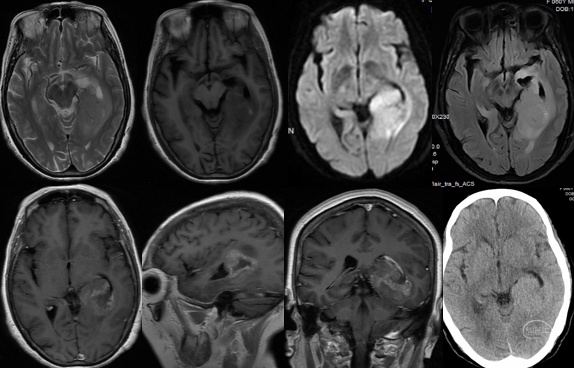

(一)左颞内侧巨大胶质母细胞瘤全切一例

患者,女,60岁,1年前出现记忆障碍伴反应迟钝,症状进行性加重,5个月前突发意识不清伴四肢抽搐1次,5天前出现头痛。

术前检查提示左颞内侧巨大占位,病灶不均匀强化,弥散明显受限。

波普检查显示典型的倒置峰,胶质瘤考虑。

术后CT、MRI检查提示肿瘤全切,术区出血水肿均不明显。